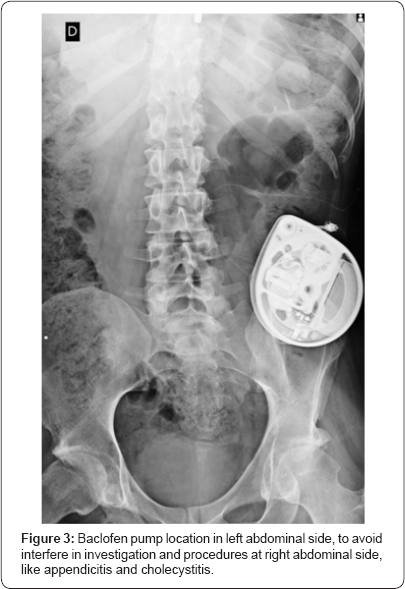

Once most abdominal diseases commonly presented in spinal cord injuried patients are at the right abdominal site, like cholecystitis and appendicitis [10], it is protocol in our service to implant baclofen pumps in left abdominal site, remaining the right abdominal side free for investigation by ultra-sound and possible surgical approaches (Figure 3), unless there is a contraindication. When ultra-sound cannot be performed, abdominal tomography or magnetic resonance may be necessary. Medtronic Synchromed 2® is compatible with magnetic resonance imagining respecting the guideline [11].